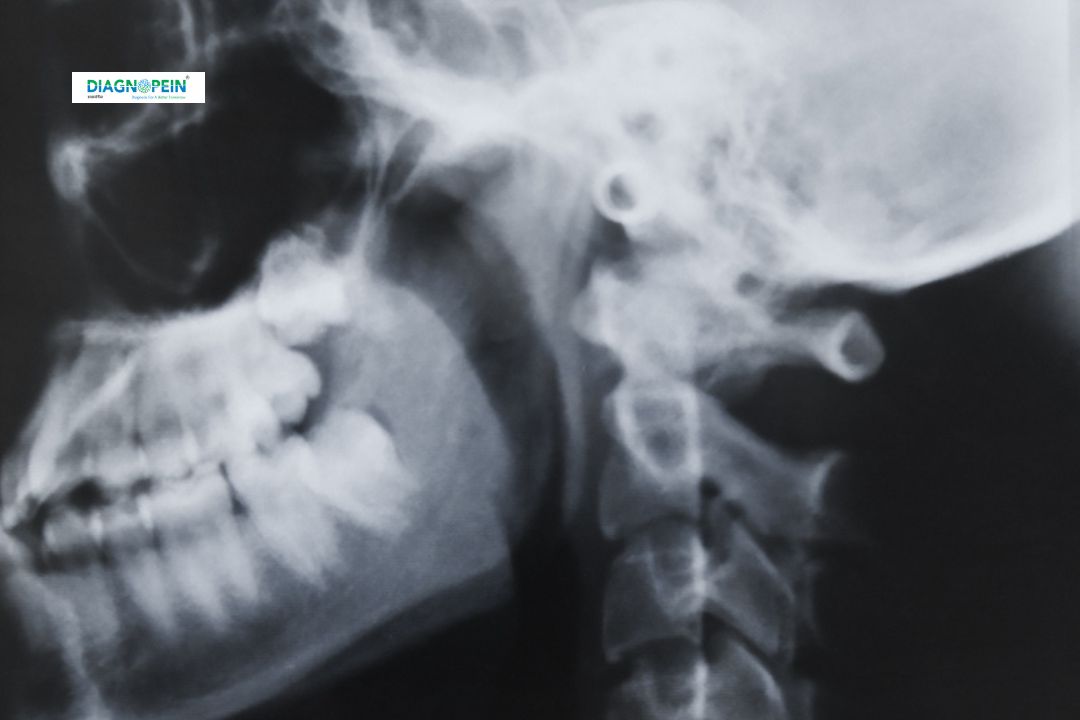

The X-Ray Barium Swallow is a specialized imaging test used to examine the structure and function of the esophagusstomach, and upper digestive tract. At Diagnopein Karad, we use advanced digital X-ray machines to provide high-quality images that help detect swallowing disorders, strictures, ulcers, and tumors in the esophagus.

During this test, the patient swallows a liquid called barium sulfate, which coats the inner lining of the upper digestive track. The barium appears clearly on X-rays, revealing any abnormalities in movement or anatomy. The barium swallow test is a non-invasive, safe, and reliable diagnostic tool frequently recommended by gastroenterologists and ENT specialists.

The X-Ray Barium Swallow plays a vital role in diagnosing conditions that affect swallowing and digestion. It provides doctors with real-time visualization of how food and liquids move from the mouth through the esophagus and into the stomach.